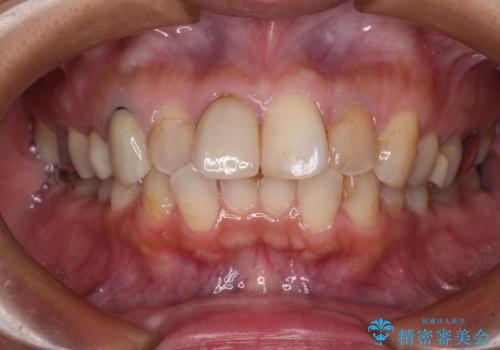

- 上下前歯のデコボコを気にして来院された患者様です。

歯列としては、ワイヤー装置でもインビザラインでも、どちらでも対応可能でしたが、処置されている歯が多く、ワイヤー装置を装着するためには処置歯のやり直しが必要な状態でした。

インビザラインでもアタッチメントを装着できないという同様のデメリットがありますが、比較的矯正治療を行いやすい歯列であったので、インビザラインによる矯正治療を行うこととしました。

術中や仕上がりに特に大きなトラブルはなく、スムーズに治療を終えることができました。